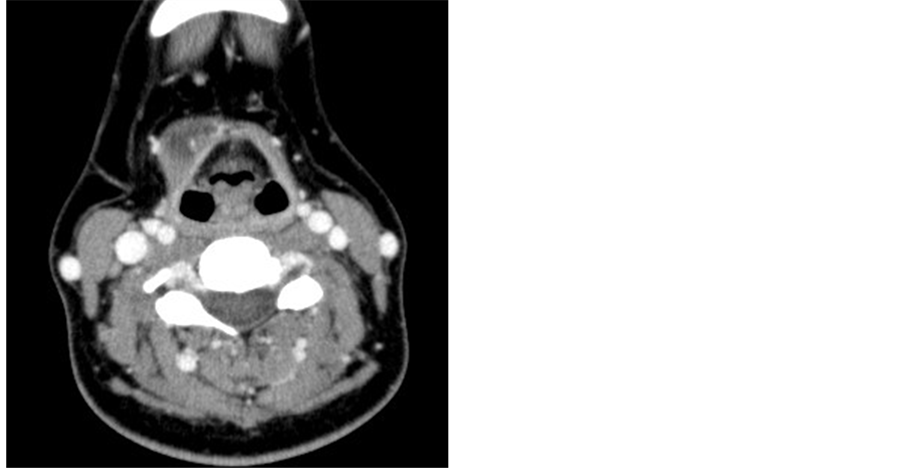

A 48-year-old woman presented to the Yokosuka Kyosai Hospital with a neck mass that had persisted for one month. She was otherwise asymptomatic. She did not have thyroid disease or radioiodine exposure previously. A smooth rubbery mass of 2 cm in diameter was located on the right ala of the thyroid cartilage. The mass was not tender and its vertical mobility on deglutition was not limited. Ultrasonography of the neck showed a well- defined hypoechoic lesion with posterior enhancement (Figure 1), but no cervical lymphadenopathy. The thyroid gland did not contain a nodule and seemed completely normal. A Computed tomography (CT) scan showed a 25 × 18 × 15 mm cystic mass on the thyroid cartilage, containing a 5 × 4 × 6 mm solid part with microcalcifications (Figure 2). Fine needle aspiration (FNA) was performed and approximately 2 ml of thin light-yellow fluid was obtained. Cytology did not provide a diagnosis in spite of the presence of some epithelial cells with irregular nuclei. FNA was not repeated because we thought the diagnosis was thyroglossal cyst. Routine blood investigations including free T3, free T4 and TSH were within normal limits.

Figure 2. Computed tomography. A 5 × 4 × 6 mm solid part and microcalcifications (arrow) were observed on the head of the tumor.